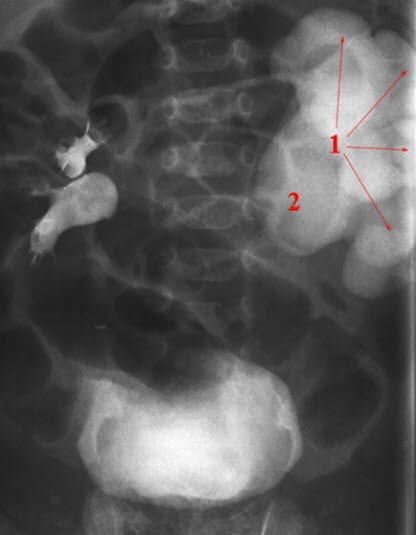

RTG, urografia: wodonercze, poszerzona miedniczka nerkowa po prawej stronie; (1) miedniczka, (2) moczowód